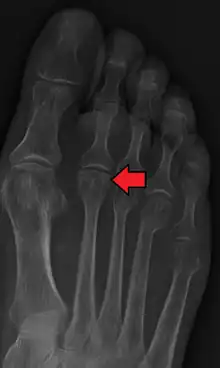

Freiberg disease as seen on plain film

Freiberg disease, also known as a Freiberg infraction, is a form of avascular necrosis in the metatarsal bone of the foot. It generally develops in the second metatarsal, but can occur in any metatarsal. Physical stress causes multiple tiny fractures where the middle of the metatarsal meets the growth plate. These fractures impair blood flow to the end of the metatarsal resulting in the death of bone cells (osteonecrosis). It is an uncommon condition, occurring most often in young women, athletes, and those with abnormally long metatarsals. Approximately 80% of those diagnosed are women.[1]